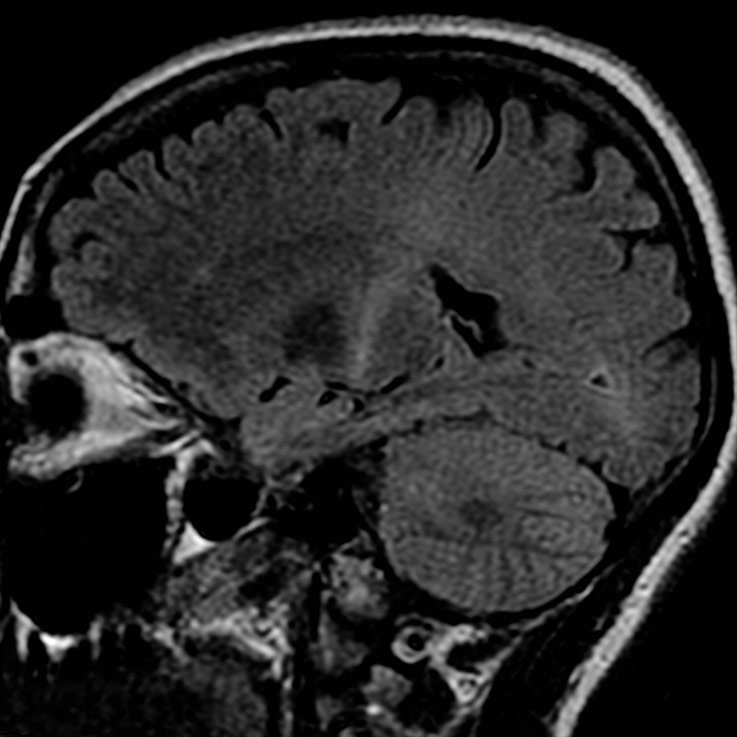

Effects of ALS in a MRI image

ANOVA IRM Germany